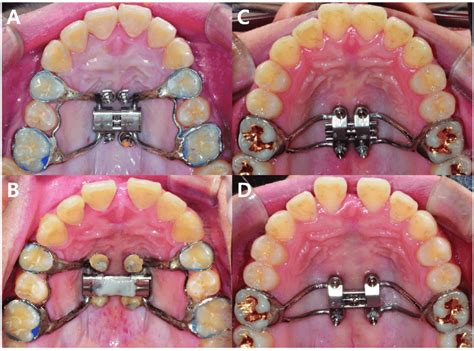

El MARPE (siglas de Mini-Implant Assisted Rapid Palatal Expansion) es un método de ortodoncia diseñado para ensanchar el maxilar superior de pacientes adolescentes y adultos jóvenes. En algunos casos, los métodos tradicionales de expansión, como las placas de expansión o los disyuntores anclados a los dientes que no se apoyan en microtornillos en el maxilar, no son suficientes para corregir ciertos problemas de alineación.

El MARPE se coloca en el centro del paladar y se ancla mediante una serie de mini-implantes. Una vez instalado, se ajusta regularmente para que pueda expandir, de manera gradual, el maxilar superior. El aparato debe ser activado diariamente por parte del propio paciente y siguiendo las indicaciones del ortodoncista.

En los últimos años ha aparecido una innovadora técnica llamada MARPE (Microimplant Assisted Rapid Palatal Expansion), basada en el anclaje de un expansor a través de microtornillos en el paladar. Esta técnica nos permite aplicar las fuerzas necesarias para expandir el maxilar sin tener que aplicar fuerzas en los dientes del paciente.

El tratamiento con MARPE empieza con un análisis del grosor y el tipo de hueso maxilar a través una radiografía ósea en 3D. Si el análisis es favorable para poder aplicar esta técnica, tomaremos unos registros en 3 dimensiones del paladar con nuestro escáner intraoral.

Expansor MARPE anclado con microtornillos.

En la fotografía anterior puedes observar un efecto muy típico: la aparición de un pequeño diastema (espacio) entre los incisivos centrales. Muchos padres se asustan al verlo, pero en la clínica siempre les explico que es una señal positiva de que el paladar se está expandiendo correctamente.